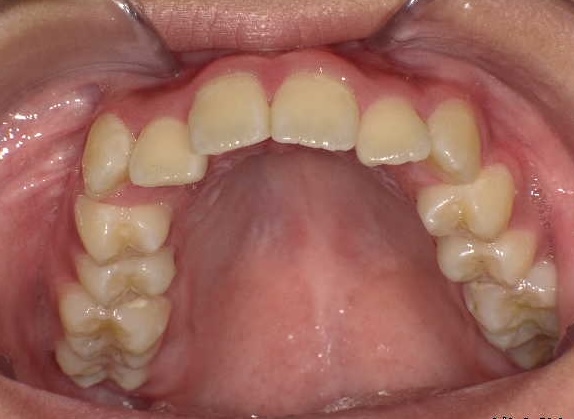

矯正前